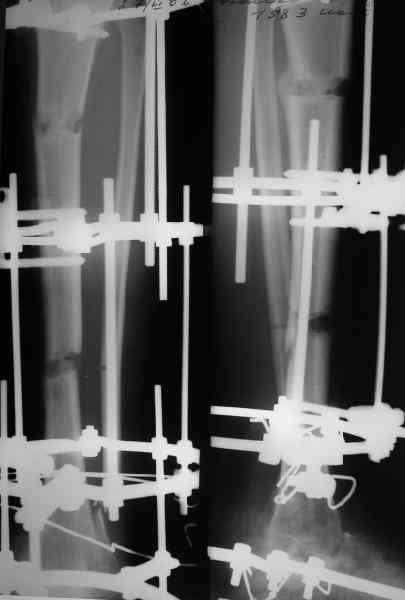

Приветствую, Павел и коллеги, ПИ> удлинения большеберцовой кости для компенсации укорочения поврежденной конечности. ПИ> В итоге: мы планируем выполнить пациенту большеберцово-пяточный ПИ> артродез в аппарате Илизарова с одновременной остеотомией берцовых В продолжение обсуждения, которое было 3 недели назад. Аналогичня операция одному нашему пациенту была сделана в конце февраля 2006. Дистракцию закончили 15 марта. На недавнем снимке нижний регенерат еще довольно хлипкий (снимок 1),

и мы не смогли обещать, что аппарат можно будет совсем скоро снять. Пациент выразил горячее желание расстаться с наружным фиксатором, даже если нужна еще одна операция. На этой неделе выполнили закрытое штифтование (впервые именно в такой ситуации) и сняли аппарат.